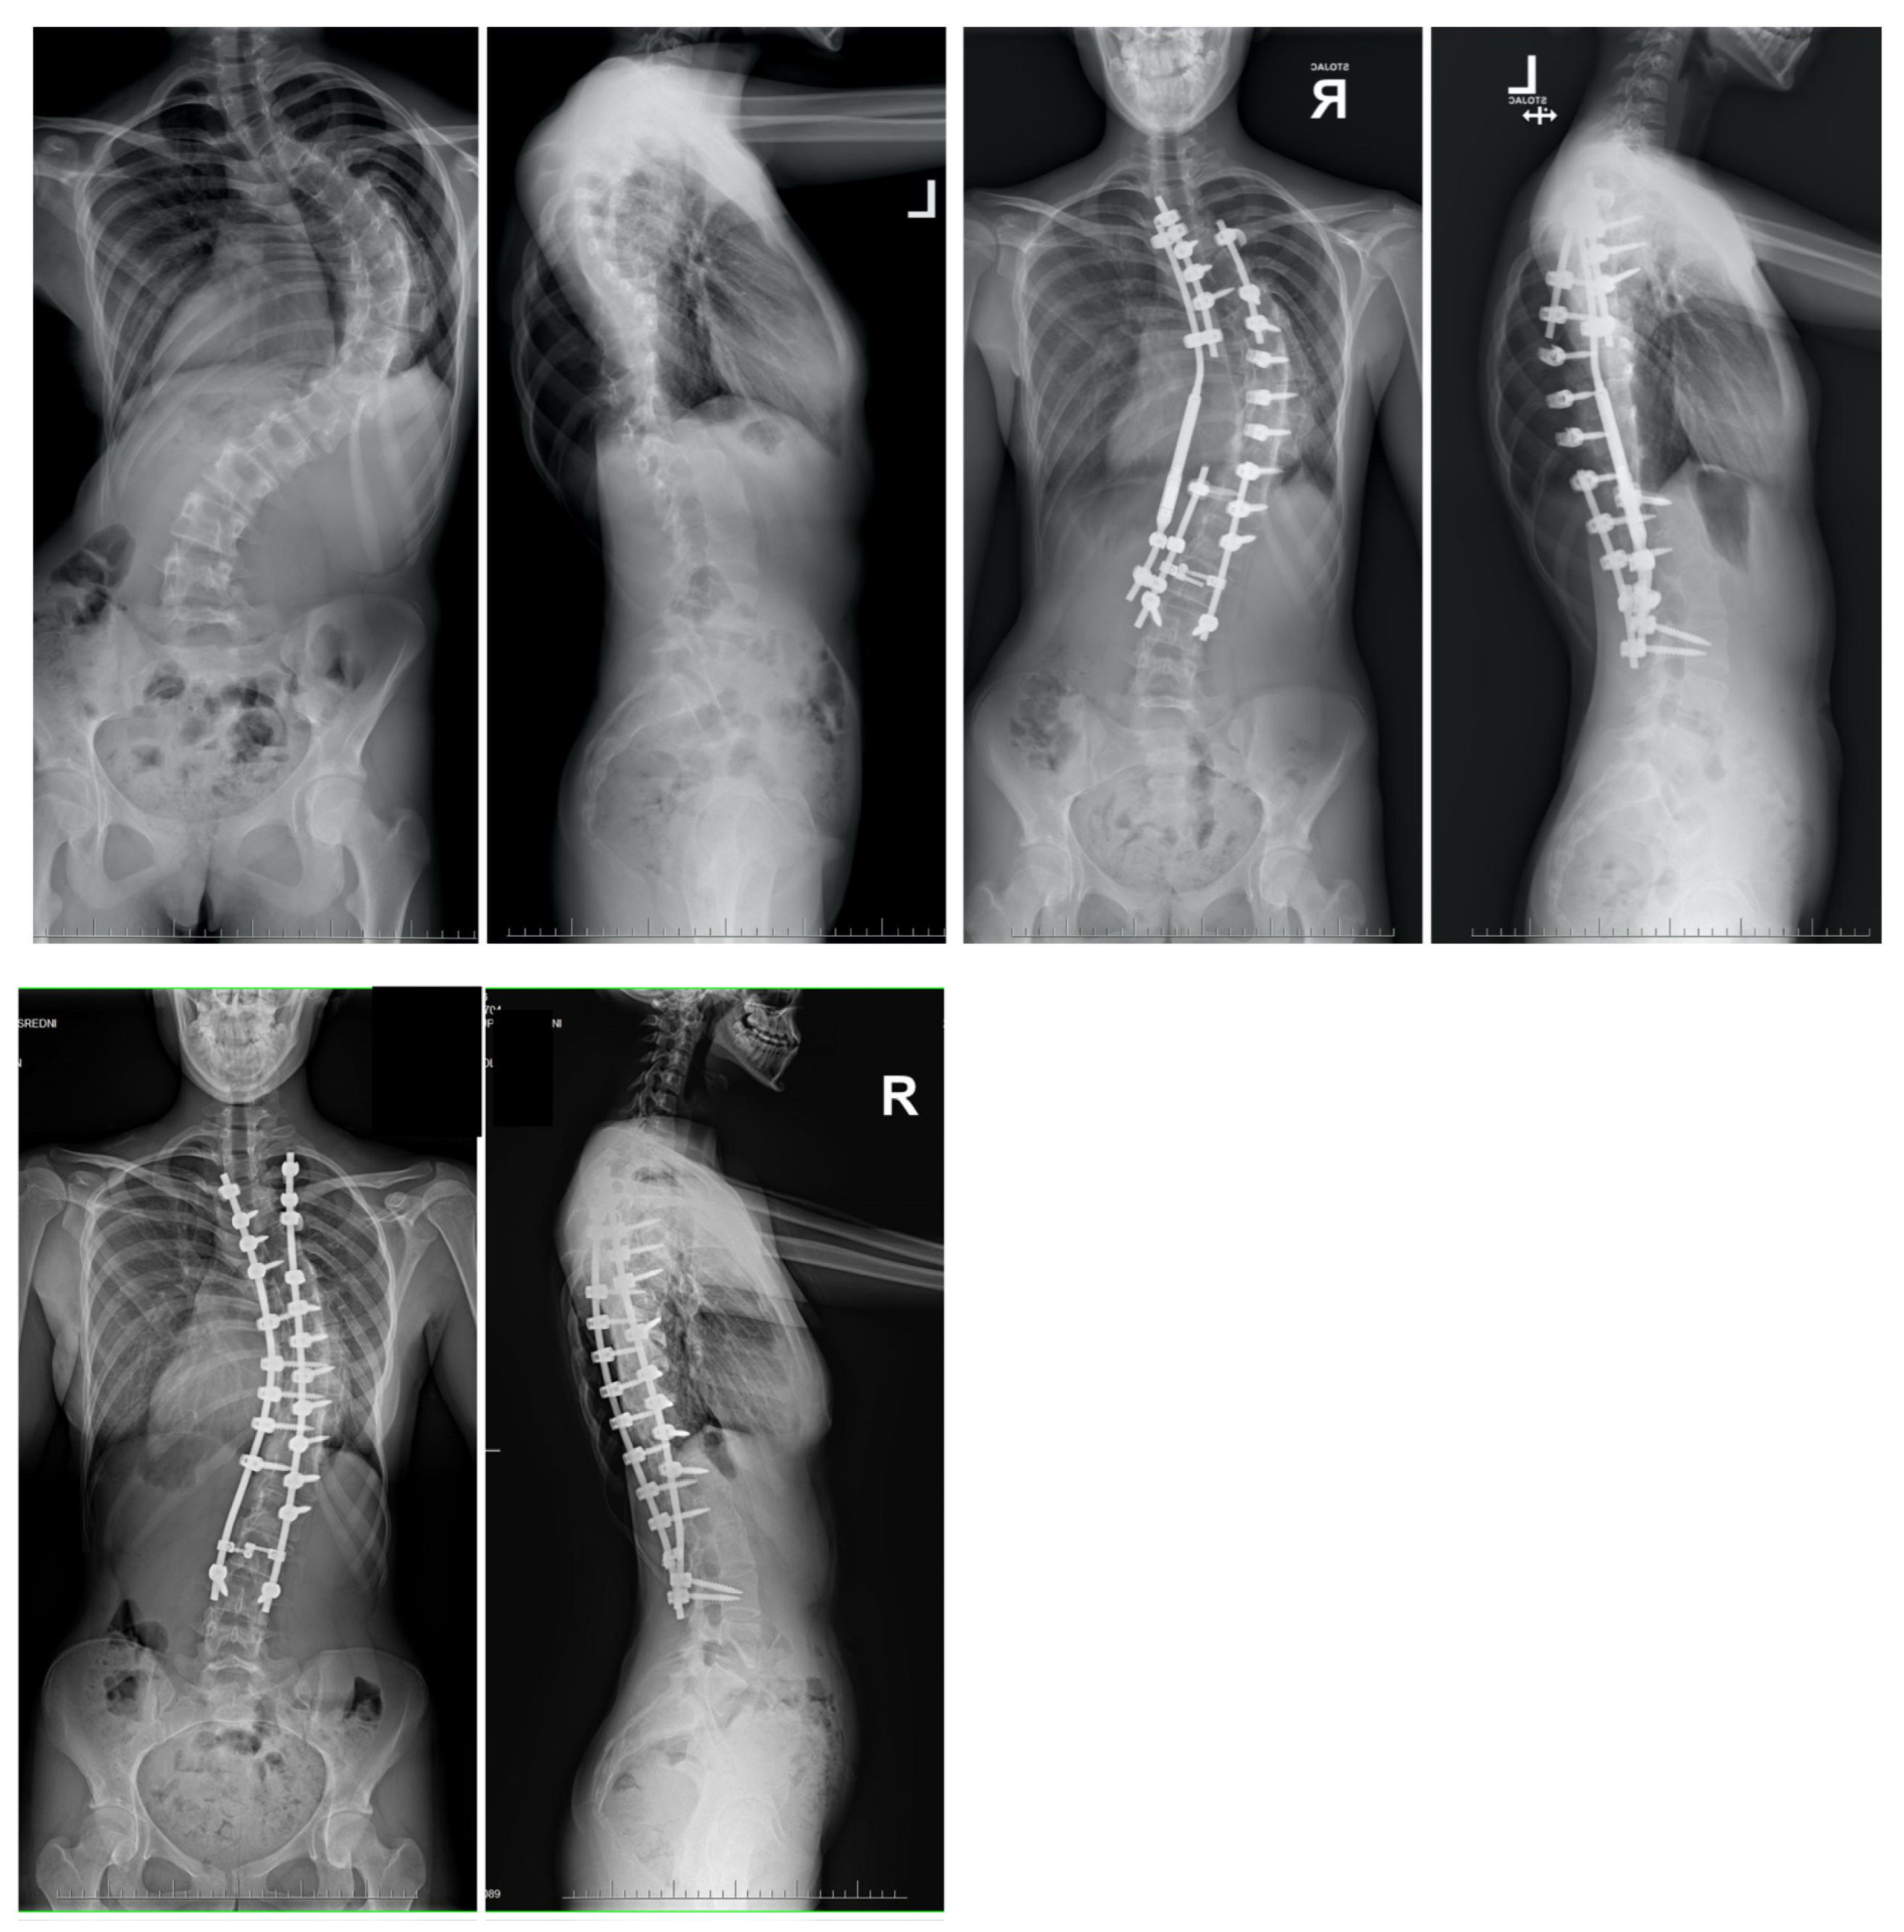

Evidence derived from numerous scientific studies suggests that patients undergoing non-vertebral column resection (non-VCR) surgical procedures are significantly more safe with less complications, than at a rate about 7 times higher, to encountering neurological complications in comparison to those undergoing VCR surgical techniques. Figure 13 showed an example of a 16-year-old boy with congenital scoliosis treated with posterior VCR and PSF. This finding underscores the importance of opting for less drastic surgical approaches when managing severe cases of scoliosis or kyphoscoliosis. Moreover, when coupled with HGT (growth-friendly techniques), utilizing these less aggressive surgical methods can lead to comparable and satisfactory outcomes in the correction of major spinal curves among these patient populations [11].

Figure 13.

An example of a 16-year-old boy with congenital scoliosis treated with posterior-only VCR and PSF followed by multi-level Ponte osteotomies, and eventual correction using double Co-chr 6.0 rods. Radiological photographs were taken both before and after the surgical intervention, as part of the observation period.